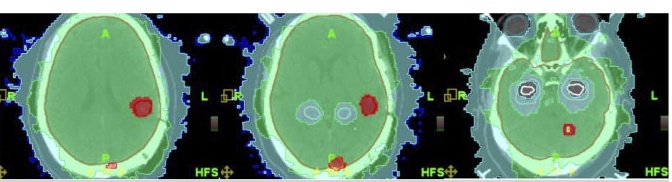

| Conformal avoidance whole brain plan

and corresponding dose-volume histogram in which the hippocampal region is conformally

avoided and the gross visible brain metastases are selectively boosted to a minimal

peripheral dose of 63 Gy. The 73 Gy (yellow), 63 Gy (red), 32.3 Gy (green), 10 Gy (sky

blue), and 8 Gy (blue) isodose lines are shown. The structures shown in the dose-volume

histogram from left to right are as follows: eyes (dark aquamarine), hippocampus (white),

hippocampus + 5 mm (light aquamarine), planning target volumes (PTV)left-temporal

metastasis (black), PTVleft-parasagittal metastasis (yellow), and

PTVcerebellar metastasis (blue). |